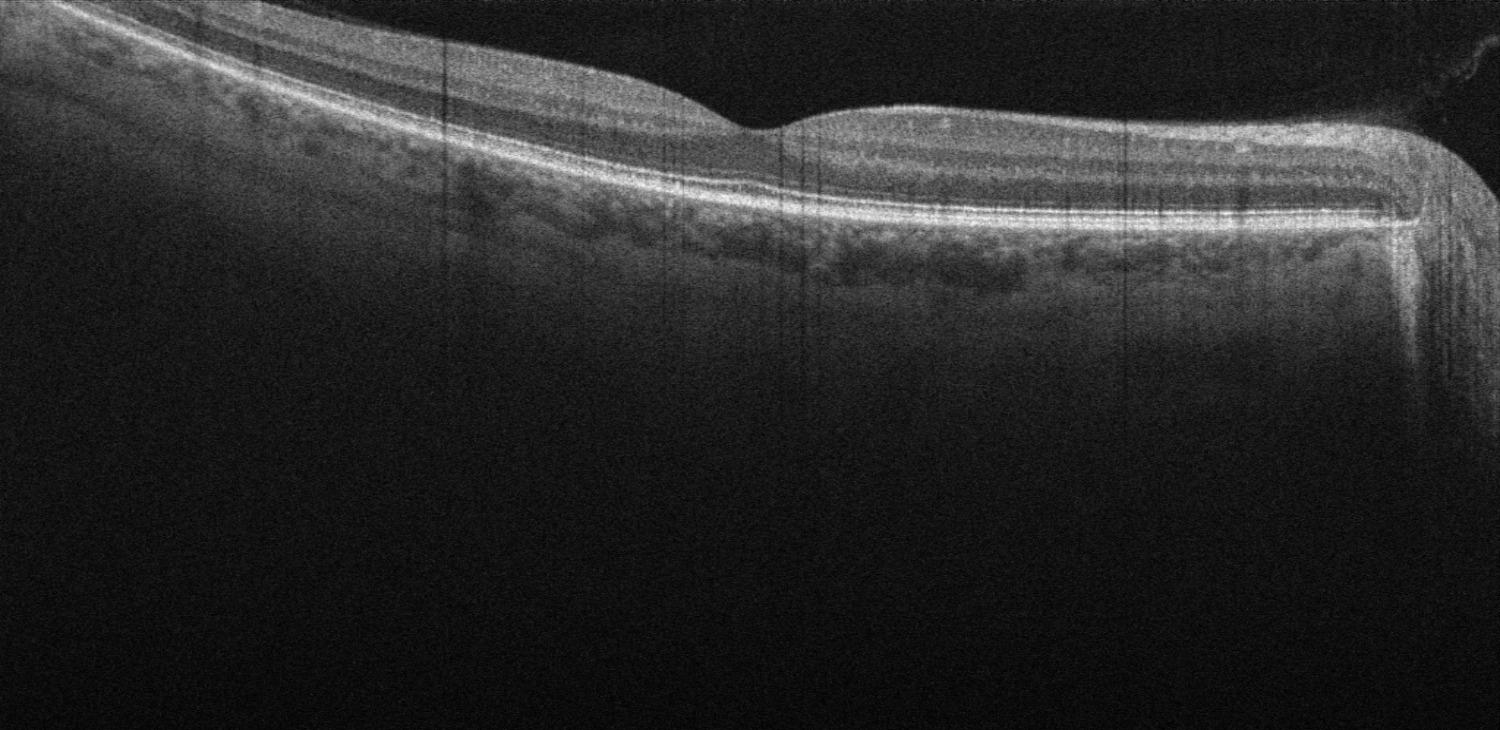

Optische Kohärenztomographie (OCT) der Macula und des Sehnervs

Die optische Kohärenztomographie bezeichnet die Netzhautspiegelung. Das Verfahren dient der Erkennung von Auffälligkeiten des Augenhintergrunds und der Netzhaut.

Der Laser des OCT liefert sehr genaue Bilder, die Veränderungen der Netzhaut, des Sehnervs und der umgebenden Gewebestrukturen sichtbar machen. Die Analyse der optischen Kohärenztomographie liefert zuverlässige Erkenntnisse, die bei der rein oberflächlichen Betrachtung der Netzhaut nicht zu sehen sein würden.